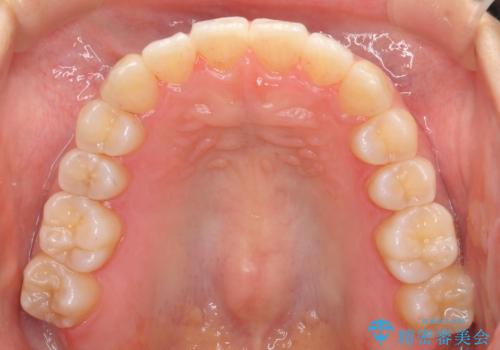

前歯のがたつき インビザラインで 下の奥歯を後ろに下げる

- 上下の前歯のがたつきを主訴に来院。

骨格的に受け口の傾向があり、下の奥歯が前方にに位置しており、下の前歯が特にがたつきが大きい状態でした。

下の奥歯を後ろに下げて下の前歯が前方に出ないように治療しました。

矯正用ミニスクリューを用いて治療しています。